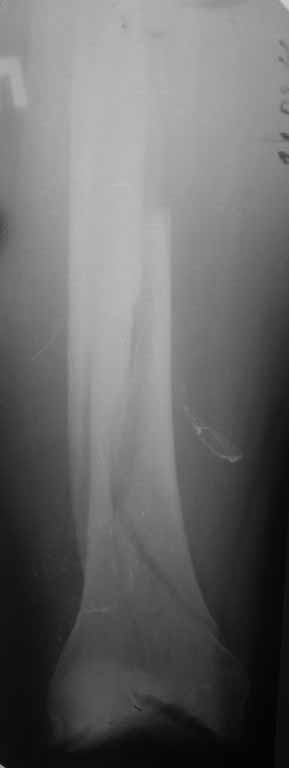

Уважаемые коллеги! 5.08.11 синтез бедренной кости пластиной LCP для дистального бедра.

Прошу совета. П-ка, 59 лет, автодорожная травма, перелом винтообразный н/3 левой бедренной кости. Планировалась закрытая репозиция и малоинвазивный доступ. по ходу операции пришлось немного открыть зону перелома для репозиции. Под контролем ЭОП вроде на столе смещение небольшое было и по оси терпимо. Сделали рентген контроль и получили вот картину. Еще обломилась головка кортикального винта. Синтез то стабильный. Только смещение не только не устранили, но кажется еще чуть больше стало (не могу) первичный снимок сделать). Склонен к ресинтезу и исправлению смещения из расширенного доступа. Как лучше выполнить репозицию? Какие можно использовать приемы репозиции? Спасибо.

Коллега,для адекватной оценки перелома необходимо предоставлять предоперационные и послеоперационные снимки в двух проекциях. Насколько возможно судить по маленькой картинке прямой проекции, на первый взгляд тут простой винтообразный перелом 32-А1. В таком случае самый стабильный вариант накостного остеосинтеза - это стягивающий винт перепендикулярно линии перелома и нейтрализирующая пластина. Особых показаний к малоинвазивному мостовидному остеосинтезу нет, т.к. при нем ниже стабильность фиксации, и все микродвижения сконтрентрируются в сравнительно небольшой зоне перелома, что приведет к большим смещающим силам. Однако, если присмотрется, на снимке видно что линия перелома продолжается до начала медиального мыщелка, поэтому скорее всего это клиновидным перелом со спиральным клином 32-В1. В таких случаях возможно выполнение мостовидного синтеза, однако в данном случае дистальная часть клина не смещена относительно дистального конца бедренной кости, таким образом, мне кажется, биомеханически ситуация представляет собой среднее между А1 и чистым В1. Смещающие усилия концентрируются в проксимальной части перелома, тогда как в дистальной несмещенной части они минимальны, в т.ч. из-за интактной надкостницы. Поэтому в данном конкретном случае, при невозможности выполнения интрамедуллярного блокирующего остеосинтеза, я бы выполнил остеосинтез с двумя стягивающими винтами (с рассверливанием ближнего кортикала сверлом большего диаметра) и нейтрализирующего остеосинтеза пластиной. Причем пластина могла бы быть даже обычная.

На представленных снимках, репозиции нет, есть вальгус. Полагаю фиксация не стабильна. Перелом может и срастется, но это будет долго и без нагрузки. Если бы была использована обычная пластина, можно было бы попробовать малоинвазивно подтянуть дистальный отломок и зафиксиривовать парой винтов. Однако примененные блокирующие винты не позволят этого сделать. Как вариант, возможно открытся снизу удалить винты, сделать небольшой доступ в зоне перелома (или попробовать закрыто) ввести 1-2 винта для фиксации клина, и перепровести блокирующие дистальные винты. В любом случае, стабильность при любом из этих вариантов будет заведомо ниже чем при стягивающих винтах + нейтрализирующей пластине. Удачи.

Для принятия решения в данном случае желательно переделать прямую проекцию на длинной кассете с захватом коленного сустава - четче оценить оси, остаточные и качество фиксации; однако и имеющийся снимок не вызывает ощущения катастрофы - вполне неплохо должно срастаться.